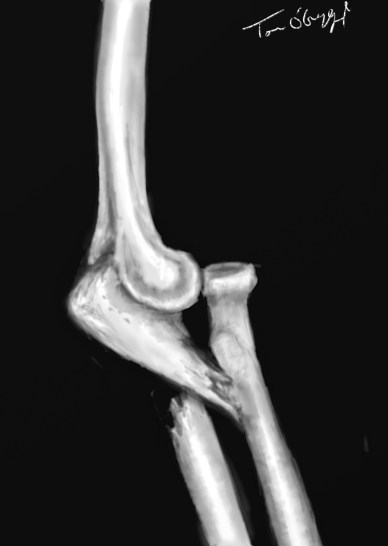

fracture de Monteggia

fracture de Monteggia : fracture de l’extrémité supérieure de l’ulna et luxation de la tête radiale